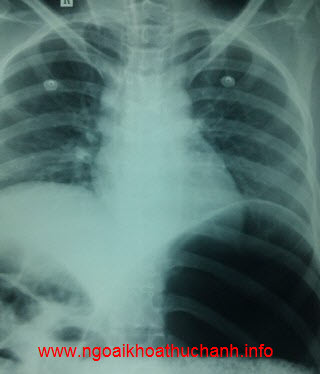

X-quang bụng cho thấy dạ dày của bệnh nhân dãn rất to, chiếm gần toàn bộ khoang bụng. Thông dạ dày được đặt, hy vọng giải áp dạ dày nhưng tình hình không cải thiện.

Bóng hơi dạ dày rất to đẩy cơ hoành trái lên trên

Dạ dày chứa đầy thức ăn chiếm gần hết khoang bụng